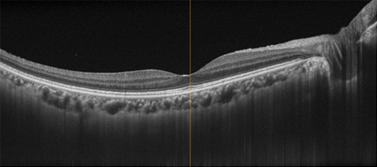

網膜の層構造を断面的に観察できます。

黄斑浮腫(網膜のむくみ)の状態がわかります。

光干渉断層画像から、造影剤を使わず非侵襲的に血管構造を画像化することができるようになりました。さらに層別に表示することができます。